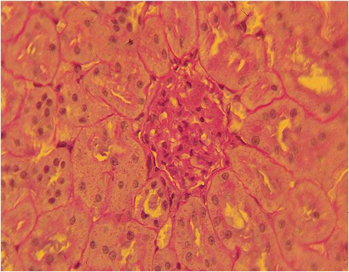

HAP INTRODUCTION IN 1 MONTH AFTER OVARIOEKTOMY

2.5 months from the start of the experiment

1 - active osteoblasts;

2 - newly formed bone tissue.

Coloring: Hematoxylin and eosin. Magnification: 400